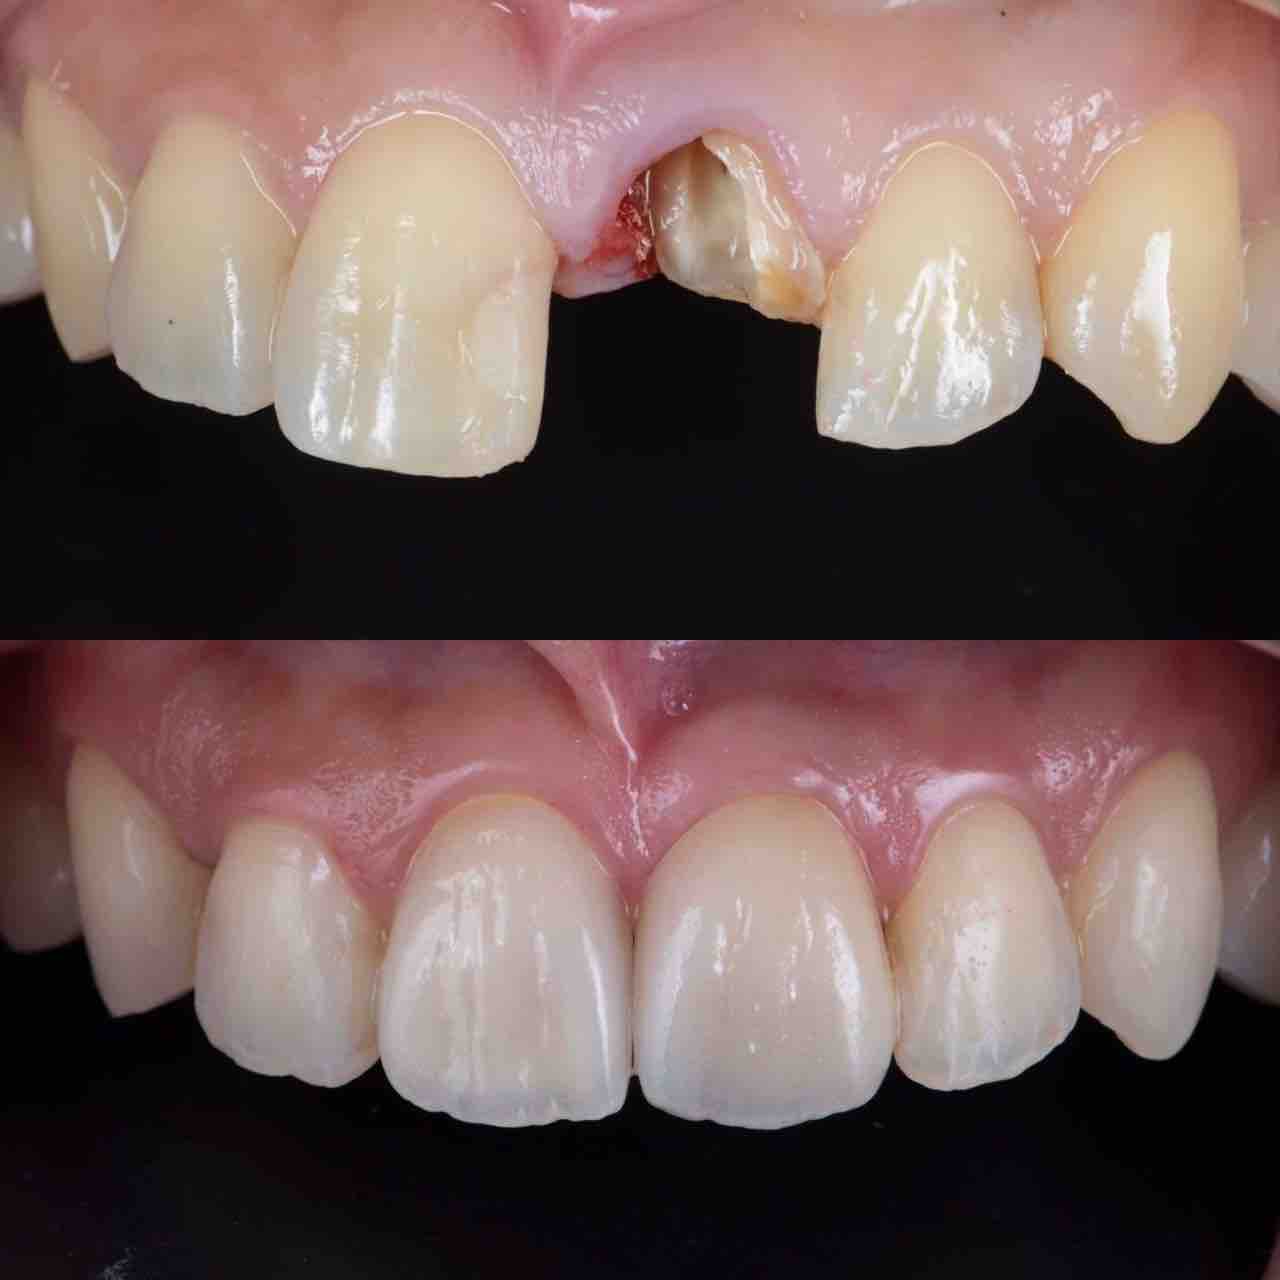

¥¤¥ó¥¹¥¿¥°¥é¥à¤ËºÜ¤»¤Æ¤¤¤ëÅö±¡¤Î¾ÉÎã¤Ç¤¹

ðÌî»õ²Ê¾ÉÎ㢠ÀèÅ··ç»¶ºÀµ¥¤¥ó¥×¥é¥ó¥È

ðÌî»õ²Ê¾ÉÎã¡¶ºÀµ¥¤¥ó¥×¥é¥ó¥È¥»¥é¥ß¥Ã¥¯